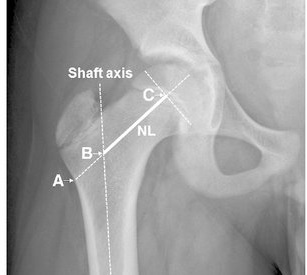

Ước tính đền bù xương đùi. Độ di lệch xương đùi được định nghĩa là khoảng cách giữa trục dọc ở giữa của xương đùi đến tâm xoay của khớp háng.